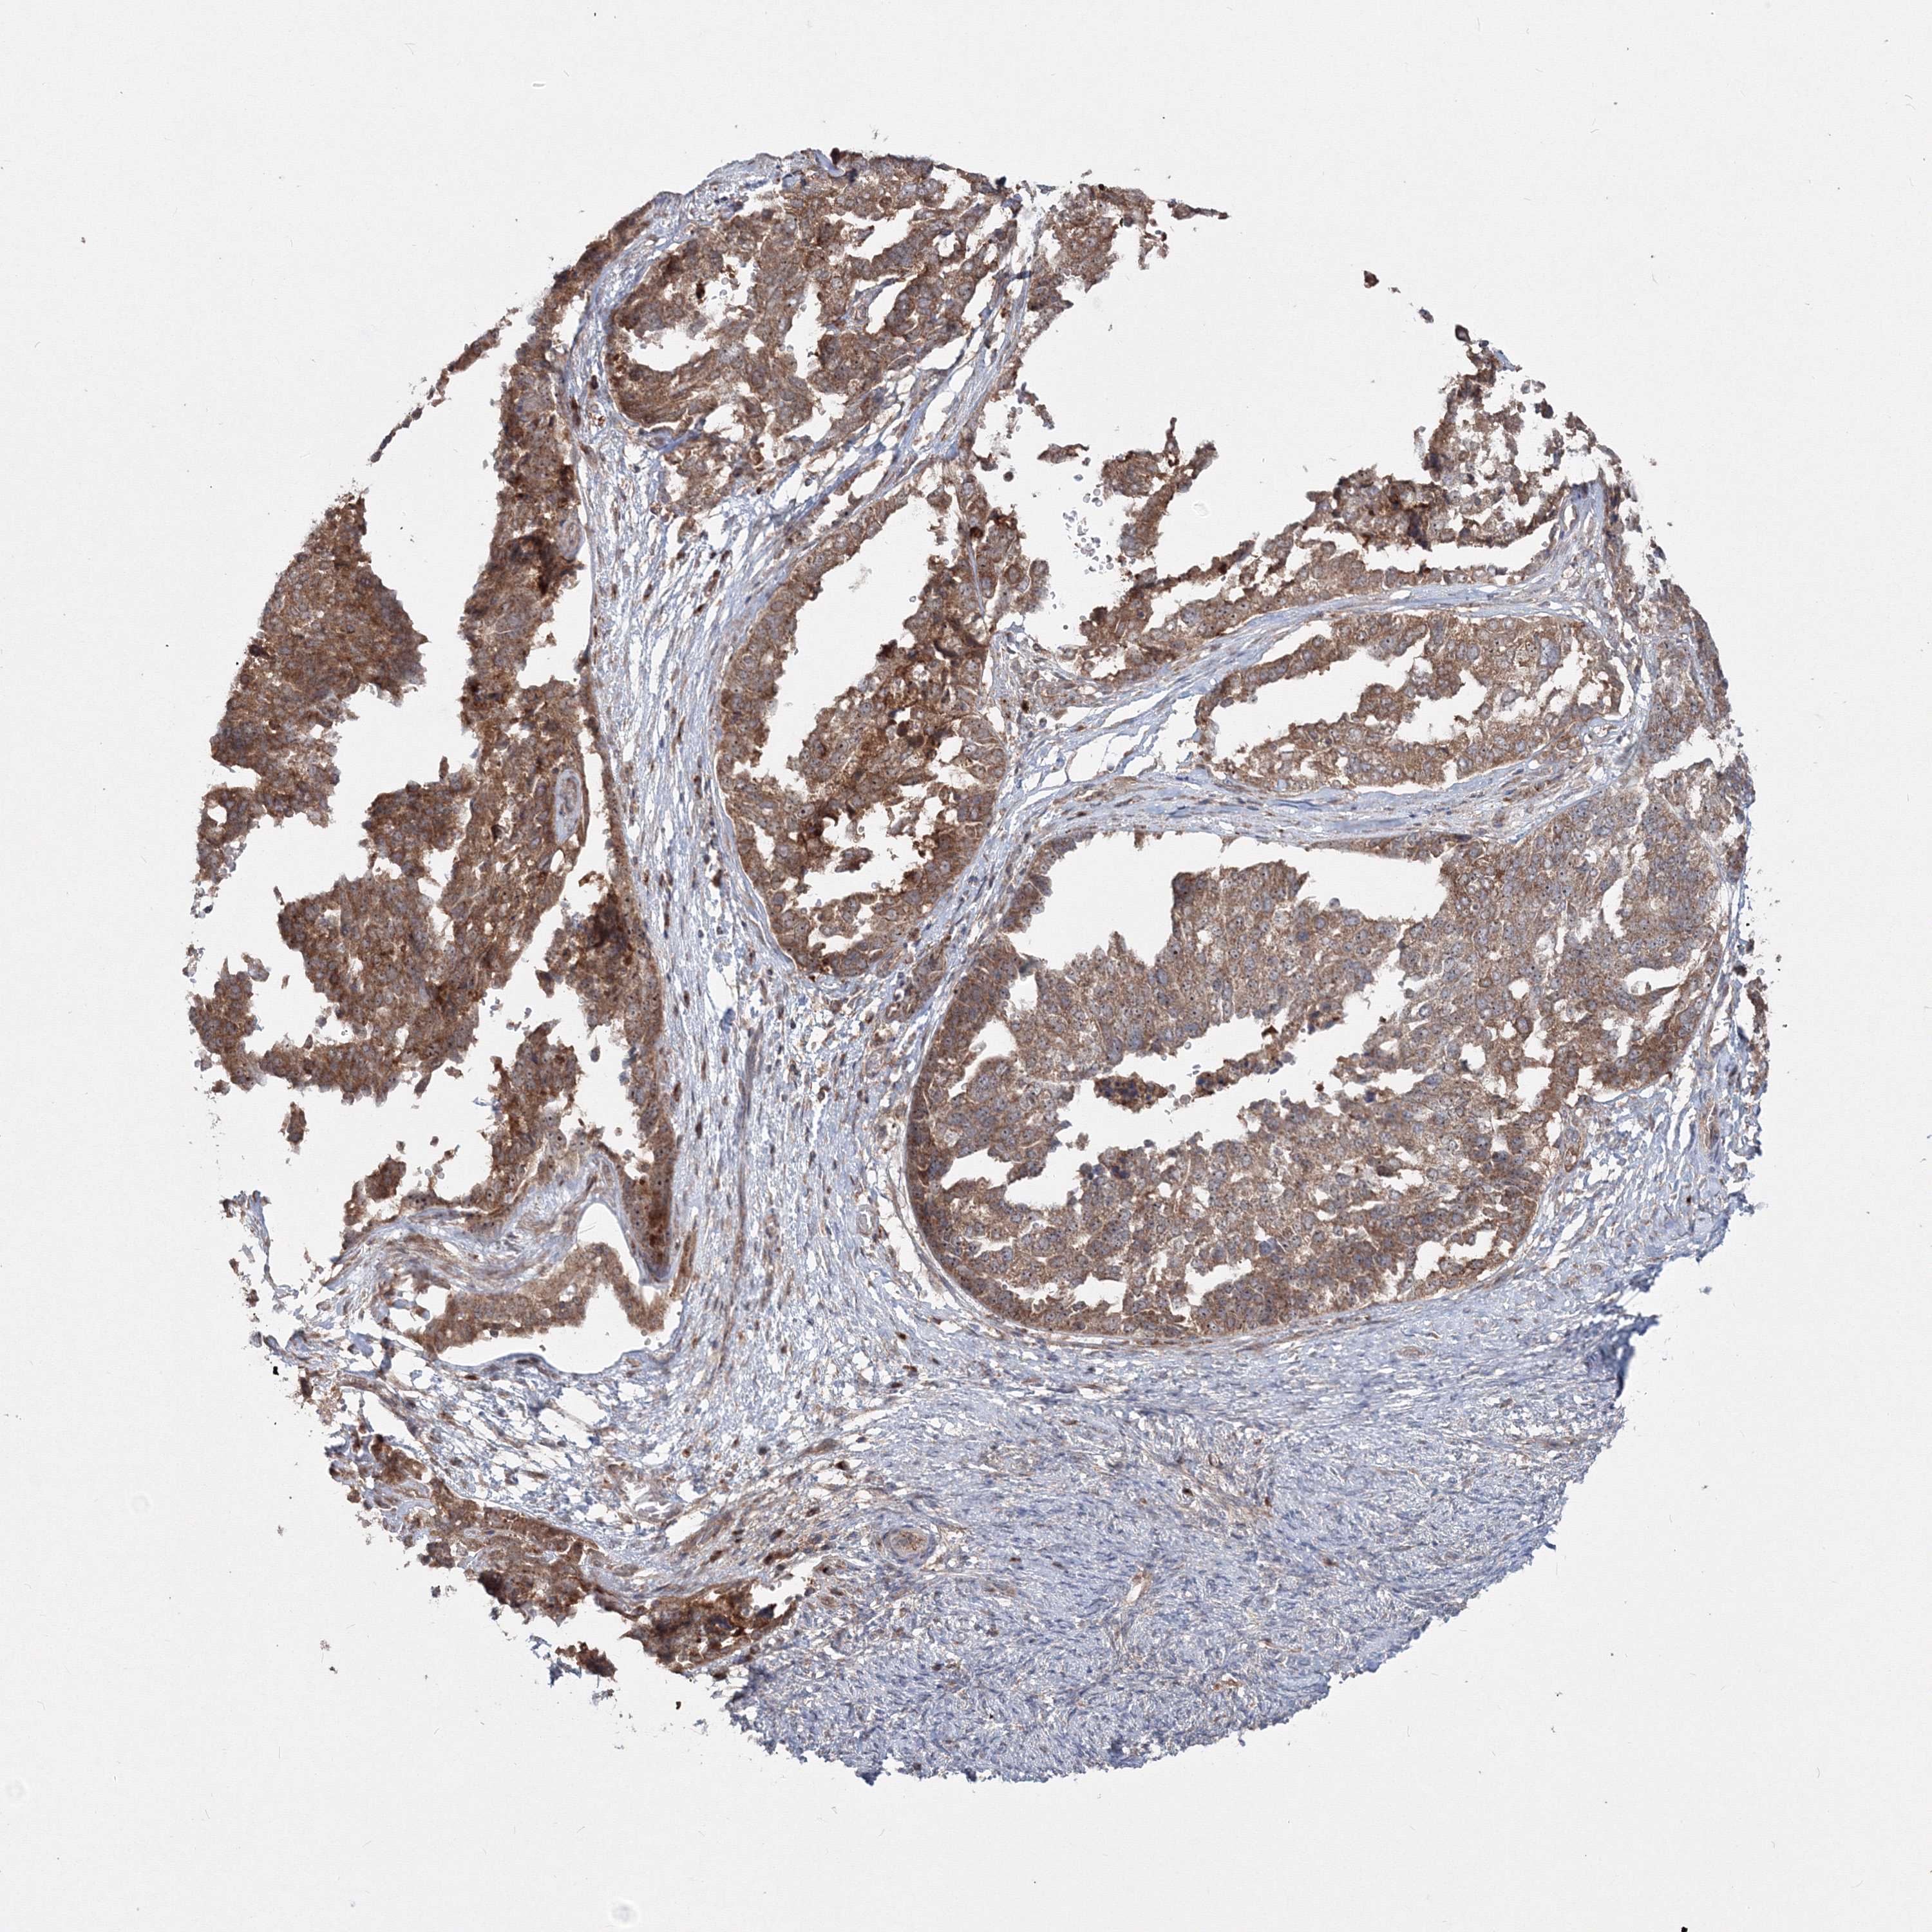

OVARIAN CANCER - Protein expressioni

A mouse-over function shows sample information and annotation data. Click on an image to view it in a full screen mode. Samples can be filtered based on level of antibody staining by selecting one or several of the following categories: high, medium, low and not detected. The assay and annotation is described here.

Note that samples used for immunohistochemistry by the Human Protein Atlas do not correspond to samples in the TCGA dataset.

Antibody stainingi

Antibody staining in the annotated cell types in the current human tissue is reported as not detected, low, medium, or high, based on conventional immunohistochemistry profiling in selected tissues. This score is based on the combination of the staining intensity and fraction of stained cells.

Each image is clickable and will lead to virtual microscopy that enables deeper exploration of all samples and also displays staining intensity scores, fraction scores and subcellular localization as well as patient and tissue information for each sample.

Antibody HPA032141

Antibody HPA032142

Antibody CAB032689

Staining

High

Medium

Low

Not detected

Intensity

Strong

Moderate

Weak

Negative

Quantity

>75%

75%-25%

<25%

None

Location

Nuclear

Cytoplasmic/membranous

Cytoplasmic/membranous,nuclear

Cystadenocarcinoma, serous, NOS

Carcinoma, endometroid

Cystadenocarcinoma, mucinous, NOS

Carcinoma, NOS